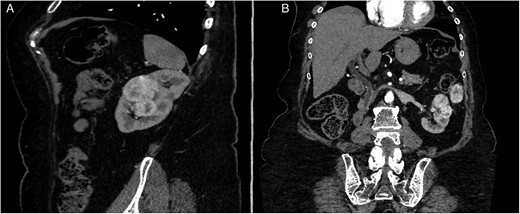

After 40 months of nivolumab exposure, no distant relapse was experienced. However, the three known lesions of the kidney and left paracolic gutter progressed in size and led to the decision of an imperative robotic-assisted double partial nephrectomy (RAPN) and concomitant metastasectomy. The patient’s preoperative assessment was Eastern Cooperative Oncologic Group (ECOG) performance status grade 0, an American Society of Anesthesiologists (ASA) physical status grade 3, with a 29-body mass index (BMI) and a stage IV renal chronic disease (serum Creatinine, sC: 156 μmol/l, modification of diet for renal disease (MDRD) equation of glomerular filtration rate (GFR): 27 ml/min/1.73 m2). The tumor stage was cT1b cN0 cM1. The renal tumor was considered a merging of two kidney lesions, measuring in total 59 mm in diameter and totally equatorial. The paracolic gutter metastasis was 40 mm in diameter (Fig. 2). The RENAL nephrometry and PADUA scores were 10ah and 11a, respectively.

Preoperative CT-scan. (A) Sagittal section. (B) Modified coronal section allowing to see the left pericolic gutter metastasis.